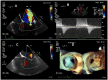

We report a case of catheter-based edge-to-edge mitral valve repair in a teenage male patient with non-ischaemic cardiomyopathy to improve pulmonary hypertension secondary to severe functional mitral regurgitation (FMR) to defer anticipated heart transplantation. A 19-year-old patient with previous history of fulminant myocarditis followed by markedly left ventricular dysfunction presented with severe mitral regurgitation 3 years after initial recovery. Slightly over time, deterioration of FMR was associated with gradual increase in pulmonary artery pressures despite optimal medical therapy. MitraClip implantation in this young patient was successfully performed with sustainable improvement of pulmonary hypertension.